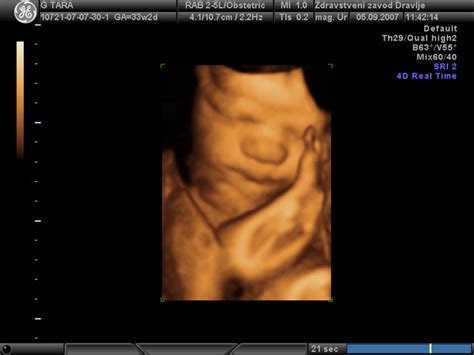

3. Ultrazvočno Določeni Datum

Zdravniki pogosto uporabljajo ultrazvok za potrditev nosečnosti in natančnejšo oceno gestacijske starosti ter s tem predvidenega datuma poroda. Ultrazvočne meritve, zlasti v zgodnji nosečnosti (približno med 8. in 12. tednom), so lahko zelo natančne pri določanju velikosti ploda, kar omogoča bolj zanesljivo oceno PDP.

Kako deluje?Če je datum poroda določen z ultrazvokom, se gestacijska starost izračuna kot razlika med trenutnim datumom in (PDP - 280 dni). Tudi zdravniki lahko na podlagi ultrazvočnih meritev ploda in dolžine materničnega vratu večkrat preverijo usklajenost PDP.